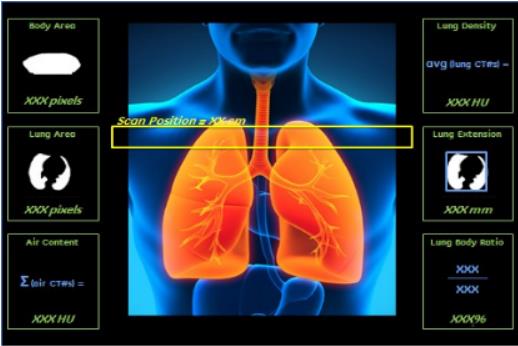

Discovery RT采用了超高端宝石CT的核心技术——宝石ASiR2.0平台,通过对原始数据采样技术、原始数据重建技术及图像数据重建等多方面技术进行革新设计,不仅能更有效地提取有效数据信息,还能在原始数据空间及图像数据空间进行三维双重迭代运算。即在不增加X线辐射剂量的条件下,降低图像噪声、提高图像分辨率,实现了全身的高清低剂量成像。

△高清低剂量成像